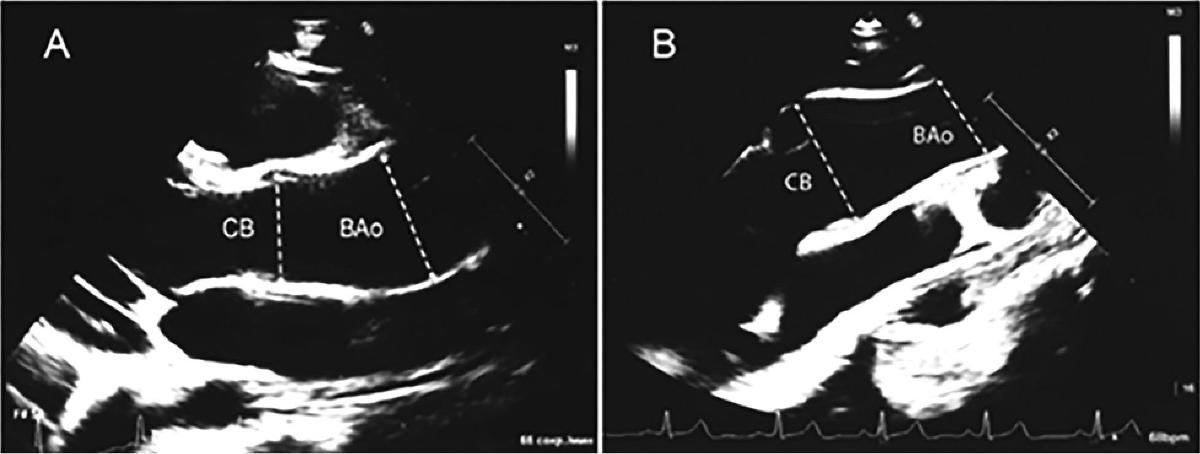

Рис. 2. ЭХОКГ двух пациентов 14 лет в парастернальной позиции по длинной оси левого желудочка после нагрузки.

A. Комбинированная дилатация аорты после нагрузки: новая для СВ (z-score 2,84, исходно 1,92) и усиление дилатации для ВАо (z-score 6,6, исходно 5,8). Дилатация СВ сочетается с дилатацией ВАо. B. Увеличение дилатации СВ (z-score 3,3, исходно 2,6) при нормальном диаметре ВАо (z-score = 1,2) возраста (7-11 лет), что может отражать прогрессирующее расширение аорты со временем (табл. 1). Однако прирост z-score для ВАо в ответ на нагрузку у них был в два раза меньше, чем у детей 7-11 лет (табл. 1), а величина прироста z-score для СВ была вообще одинаковой (табл. 1). Возможным объяснением может быть возросшая с возрастом ригидность аортальной стенки.